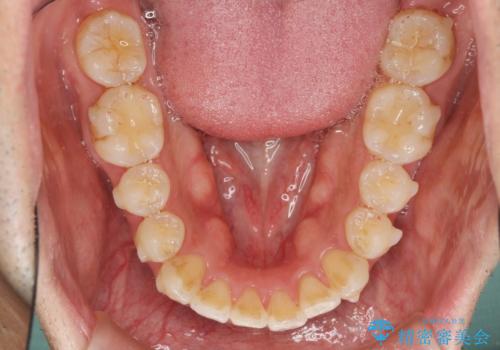

- 前歯のガタつきをきれいにしたい、と矯正治療を希望され来院されました。

マウスピース矯正インビザラインを用いてガタつきをきれいに並べていきます。

外側に傾斜していた前歯の角度も良くなり、「前歯の見た目が良くなった。」、と喜んでいただくことができました。